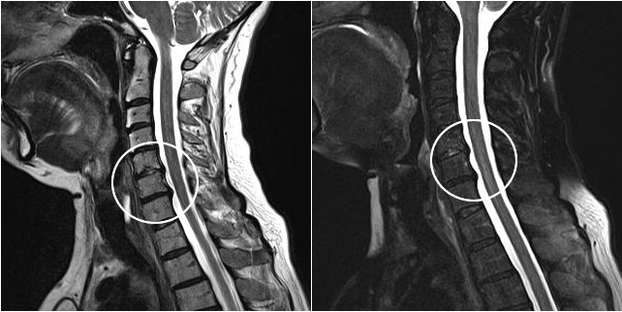

Modern diagnostic methods include MRI and CT, which allow to check the processes of destruction of cartilage and bone tissue in the most accurate way.Also, using this technique, it is convenient to diagnose hernias and other soft tissue defects close to the source of the disease.